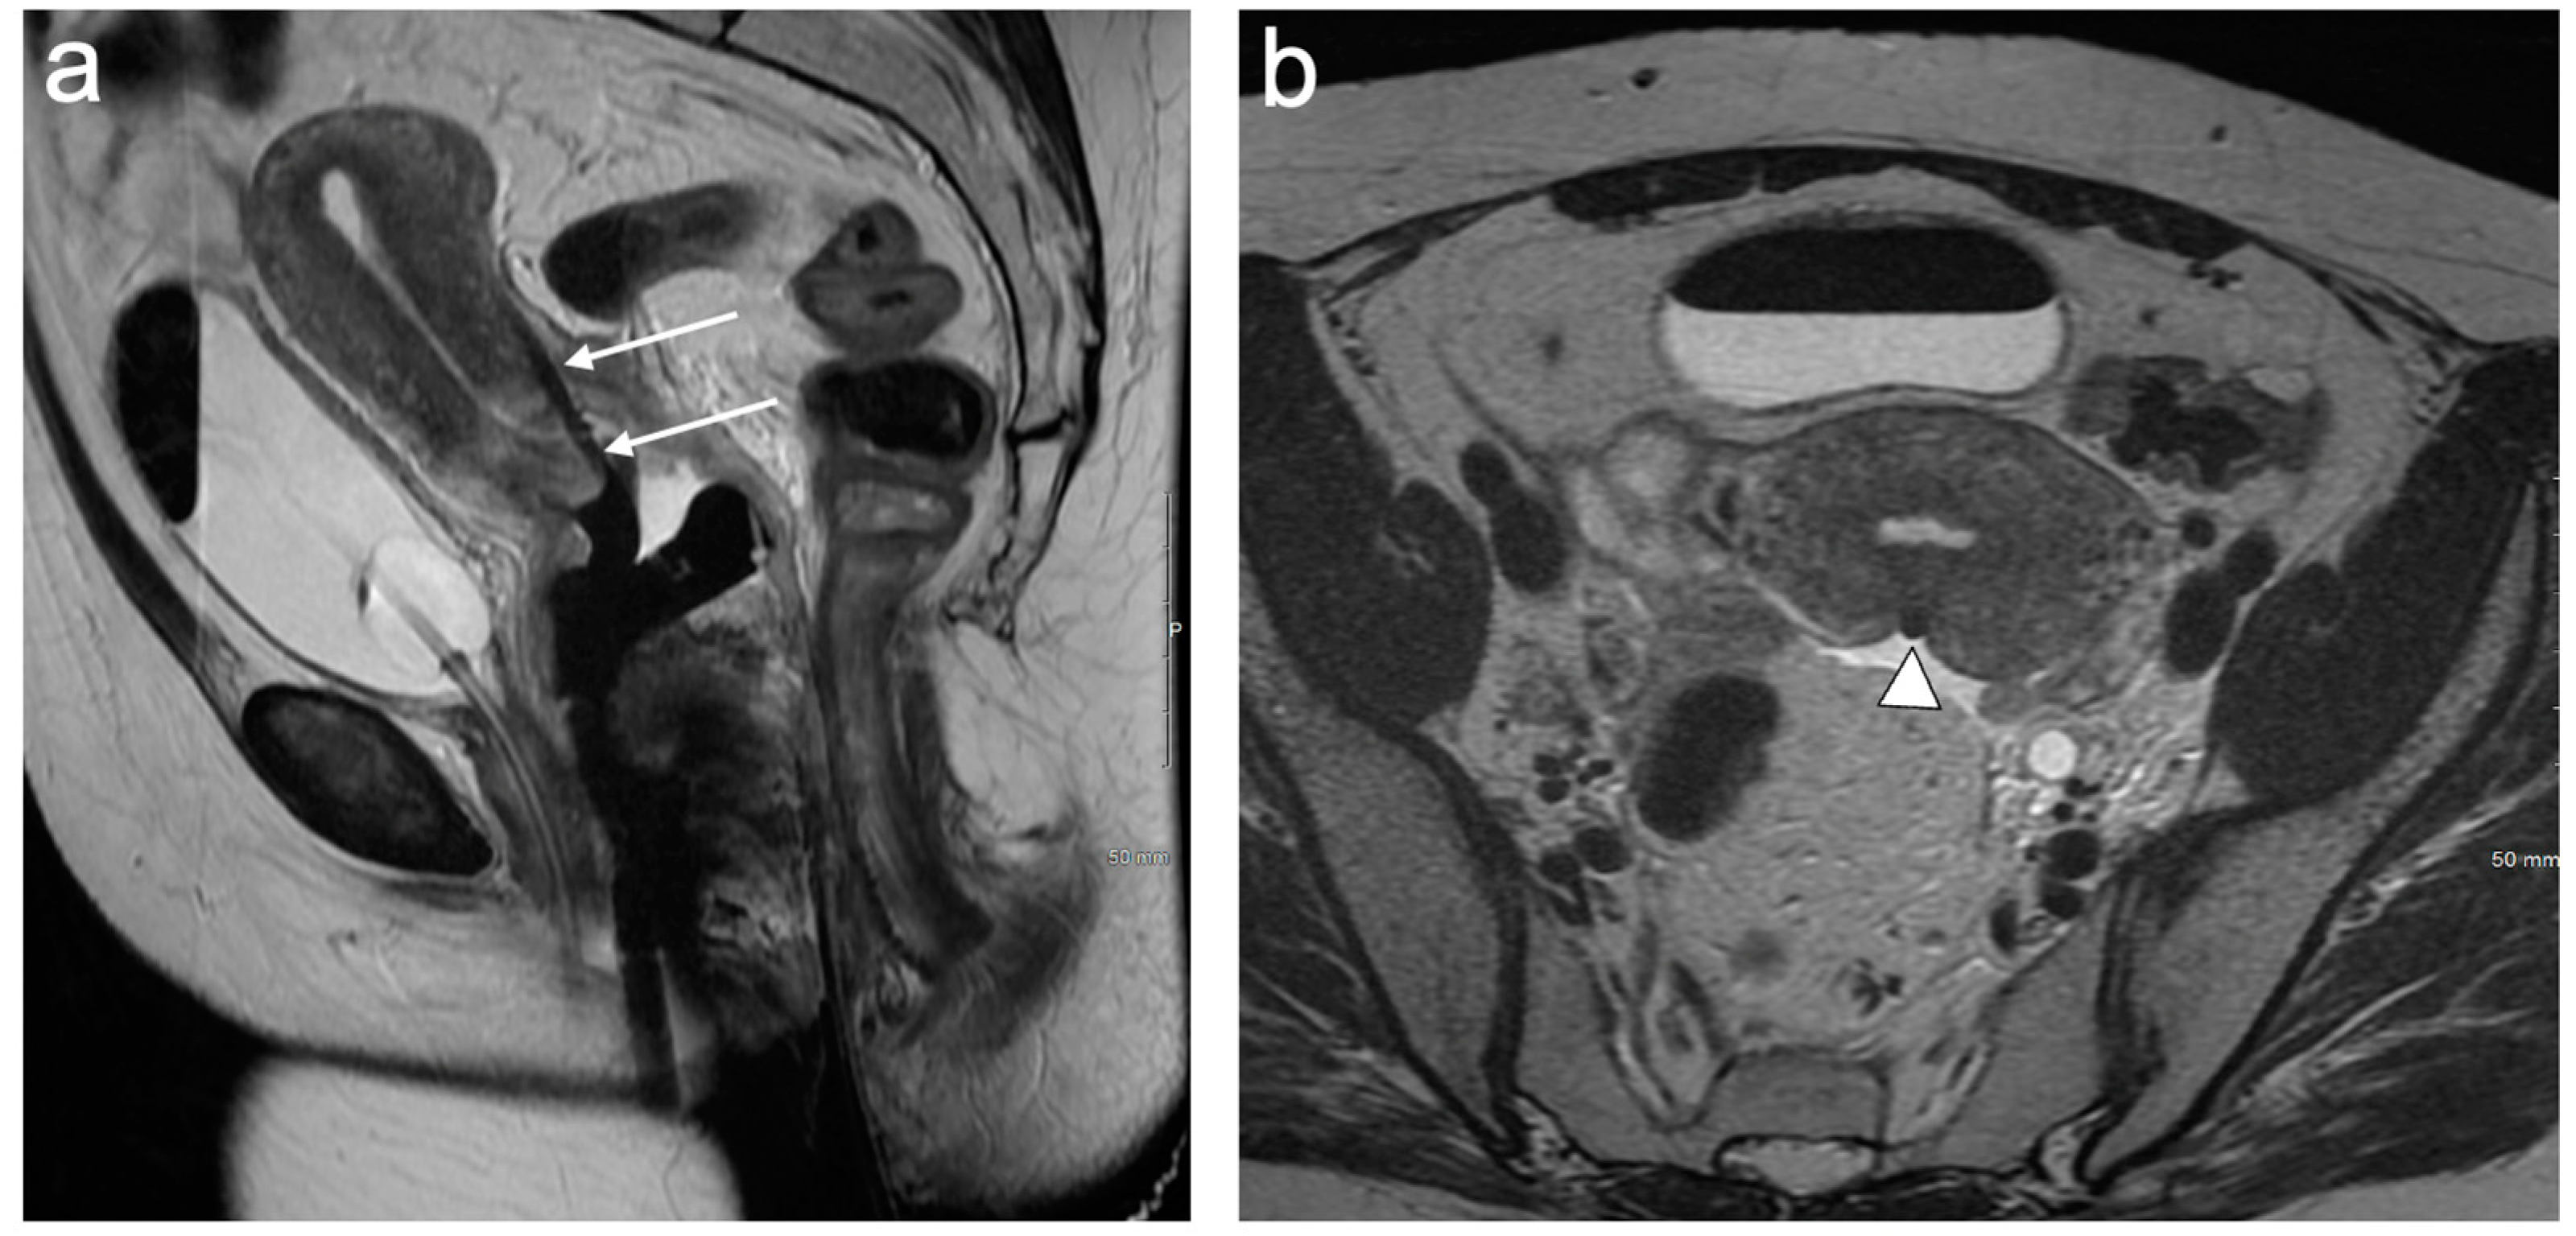

4. FIGO Stage I

5. FIGO Stage II

6. FIGO Stage III

7. FIGO Stage IV